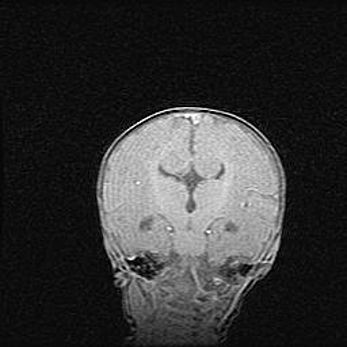

Сообщающаяся гидроцефалия. Кистозная энцефаломаляция головного мозга.

Возраст: 3 месяца 4 дня

Вес: 3100 г

Пол: женский

Окружность головы: 34 см

Срок гестации: 31 неделя

Кистозная энцефаломаляция головного мозга - одна из форм поражения головного мозга в детском возрасте. Характеризуется возникновением множественных и распространённых кист в коре, белом веществе и подкорковых образованиях головного мозга у плодов, новорождённых и детей раннего возраста. Развитие кистозной энцефаломаляции связано с внутриутробной асфиксией и гипотонией, родовой травмой, тромбозом синусов, пороками развития сосудов, инфекциями, сепсисом и другими причинами. Наиболее значимые инфекционные агенты: вирусы простого герпеса, цитомегалии, краснухи, токсоплазмы, энтеробактерии, золотистый стафилококк и другие.